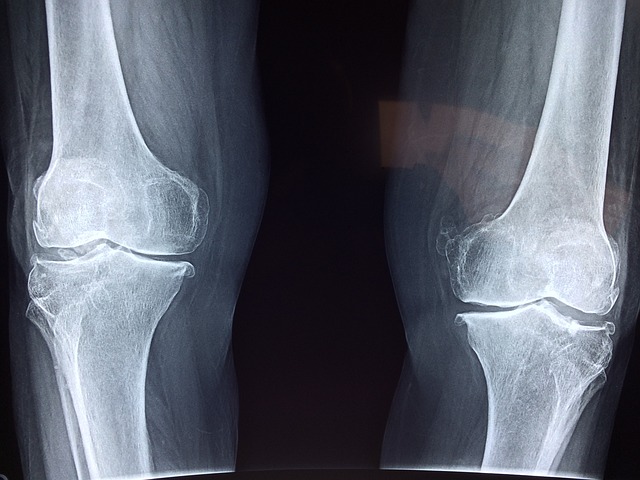

Az ízületi fájdalmak komoly gondot jelenthetnek mindazok számára, akik aktív életet élnek, vagy akik ízületi problék miatt korlátozva érzik magukat a mindennapi tevékenységekben. Az MSM (metil-szulfonil-metán) egyre népszerűbb étrend-kiegészítő azok körében, akik enyhíteni szeretnék az ízületi fájdalmaikat. De valóban hatékony? Ebben a cikkben bemutatjuk az MSM szerepét az ízületi egészség megőrzésében, tudományos kutatásokat és tapasztalatokat is figyelembe véve.

Az MSM segíthet fenntartani az ízületek rugalmasságát, ami különösen fontos azok számára, akik osteoarthritisben vagy egyéb degeneratív ízületi betegségben szenvednek.

A kén nélkülözhetetlen a kollagén és a glükozaminoglikánok termelésében, amelyek hozzájárulnak a porcok egészségéhez és regenerációjához. Egyes tanulmányok szerint az MSM együtt alkalmazva glükozaminnal és kondroitinnel jelentősen csökkentheti az ízületi kopás tüneteit.

Több klinikai vizsgálat azt is kimutatta, hogy az MSM enyhítheti az ízületi fájdalmat, ami hozzájárulhat az életminõség javításához.